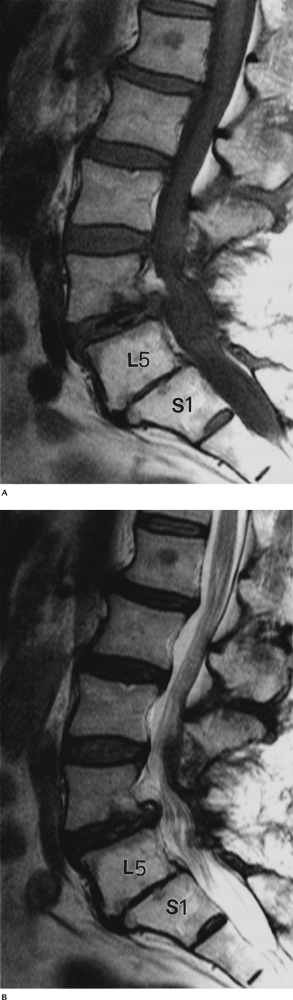

FIGURE 3-47 Type I endplate changes. Sagittal T1-weighted (A) and T2-weighted (B) images demonstrate decreased signal relative to marrow on T1-weighted (A) and increased signal on T2-weighted (B) images.

|